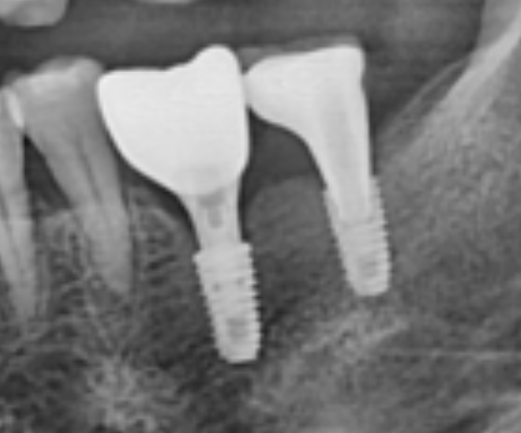

위 사진의 경우, 큰 어금니 2개가 상실되어 임플란트도 2개를 심어 회복한 모습입니다.